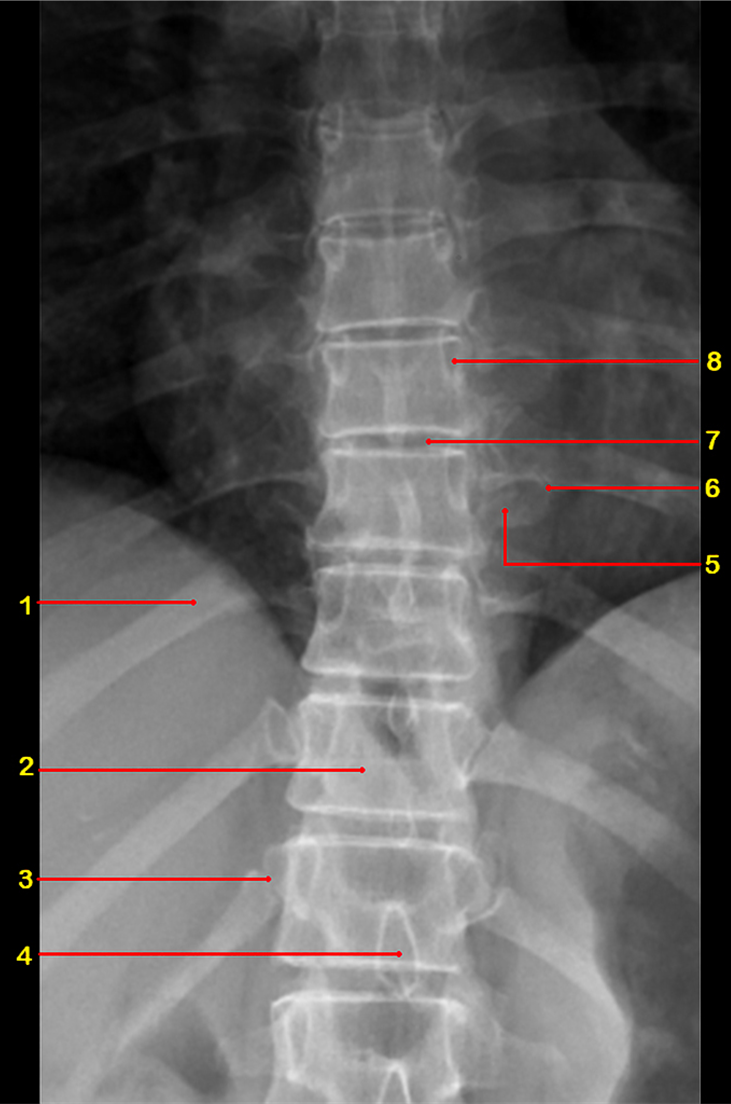

What is 1

rib

What is 2

vertebral body

What is 3

costovertebral joint

What is 4

spinous process

What is 5

transverse process

What is 6

costotransverse joint

What is 7

intervertebral disc

What is 8

pedicle

What view is this

AP